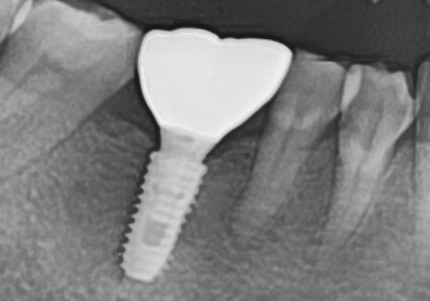

"뼈가 심하게 녹았는데

잇몸치료로 뼈가 차올랐어요"

Before

After

심한 잇몸병으로 뼈가 많이 녹은 상태

잇몸치료와 뼈이식으로 뼈 재생 후 임플란트 식립